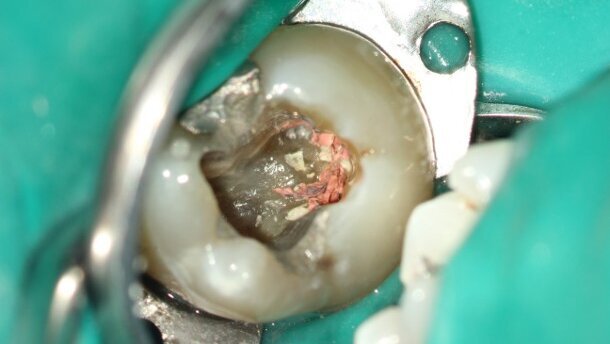

Fig. 3_Opening cavity.

Initially, the tooth was isolated with a rubber dam and an opening cavity was created through the amalgam restoration (Fig. 3). The canals were located and the opening cavity finished. Using a Pro-File 25.06 rotary file (DENTSPLY Maillefer) at 300 rpm, the gutta-percha was removed. No chloroform was necessary, as it appeared that the canals had been filled using a single-cone technique. As mentioned above, this technique might not be an ideal obturation technique. However, a more striking problem became apparent. The two palatal canals were separated by a piece of calcified pulp tissue (Fig. 4). These pieces of tissue harvest an incredible amount of bacteria and if they are not removed, they can easily lead to persistent infection. It is not always easy to distinguish the calcified tissue from (tertiary) dentine and if the dentist does not use magnification, it is practically impossible.